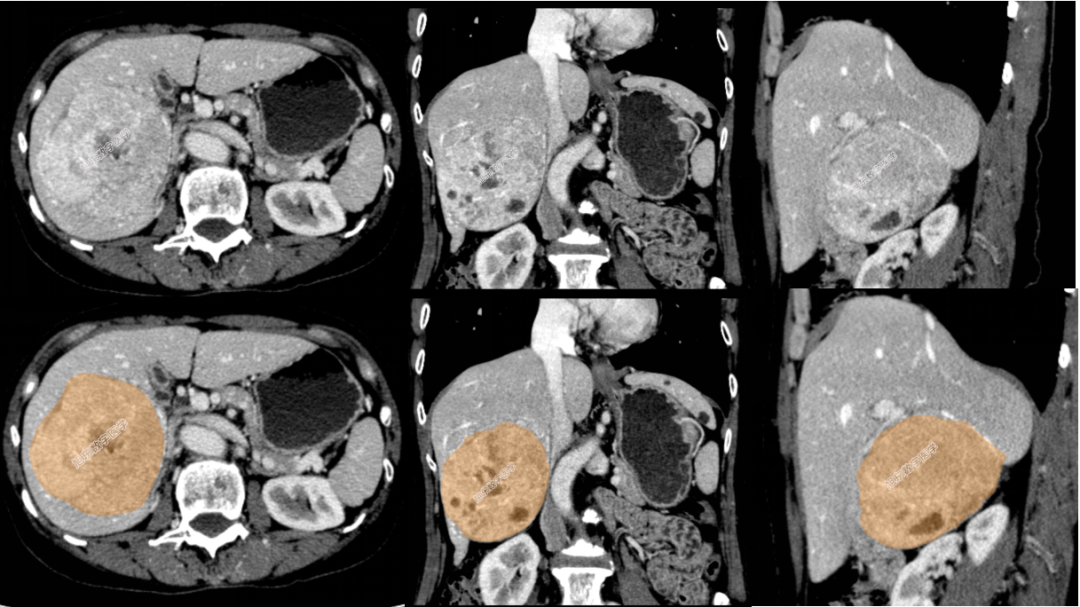

二维CT图

三维可视化术前影像评估

三维可视化全景影像图

占位与动脉血管解剖关系

占位与门静血管解剖关系

占位与肝静脉解剖关系